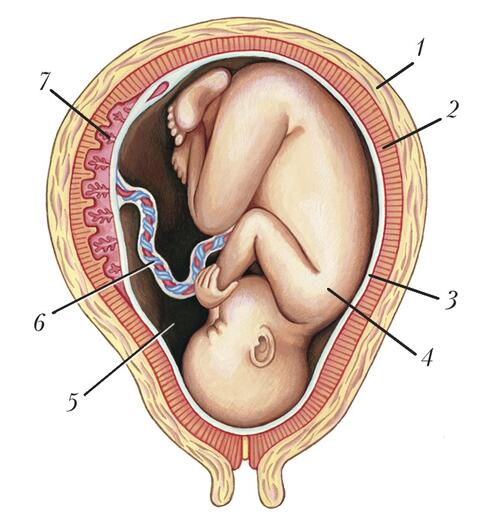

Физиология беременности: строение органов

Раздел: Моменты озарения